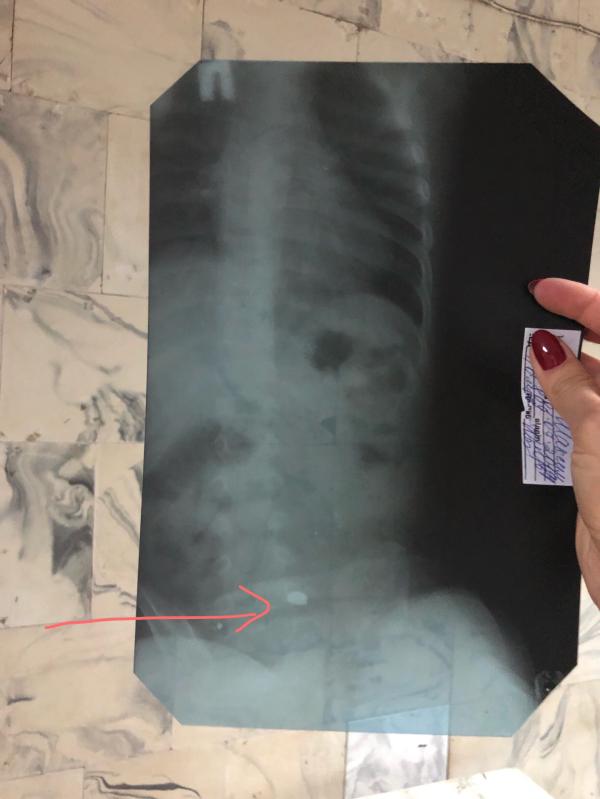

🔋Сын проглотил батарейку 🔋

1.5 года

Та, что таблеткой. Забегая наперёд, скажу что все хорошо закончилось, но если хотите подробностей, читайте ниже.

Вечером пошла Ане чистить зубы, в это время Макс нашел фонарик и разобрал его. Подошел ко мне, смотрю — жует. Понимаю что не еду. Спрашиваю: что во рту? Говорит «кака» и смеется. Подставляю руку чтобы выплюнул и офигеваю: на ладонь выпадают две батарейки. Я бегом искать источник батареек, вижу на полу фонарик. Сопоставила — одной батарейки нет. ...